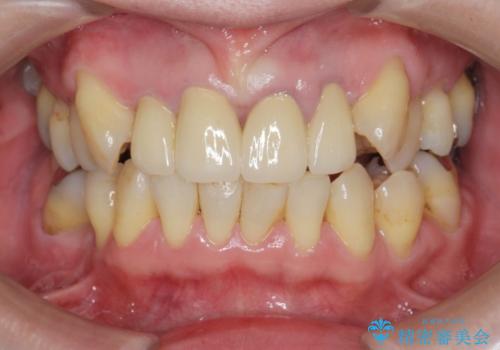

オールセラミックによる審美的な仕上がりに満足いただくことができました。